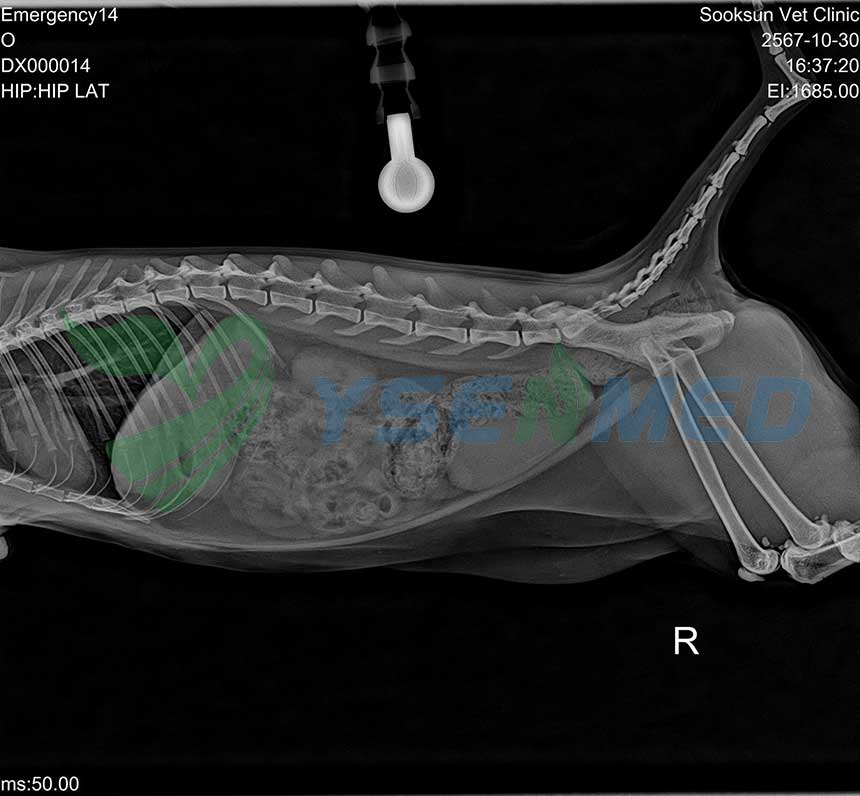

A Thai vet clinic digitizes its analog x-ray system with YSENMED YSFPD-M1717V VET flat panel detector, and the vet is very satisfied with the quality images and our after-sale service.